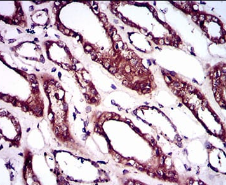

IHC    1/200 - 1/1000